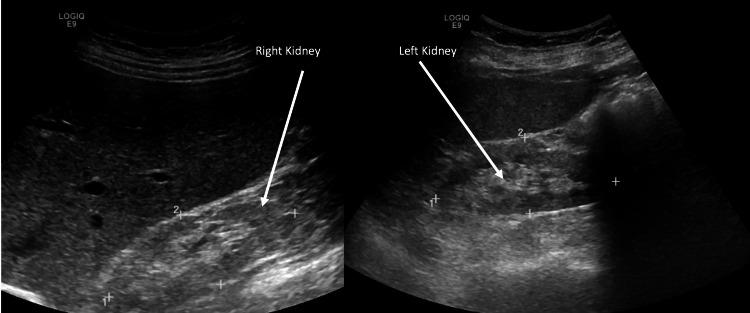

Oxalate nephropathy represents a frequently overlooked etiology of renal failure, characterized by the deposition of calcium oxalate crystals within the renal parenchyma. This progressive form of kidney disease is marked by a significant increase in serum creatinine (Cr) level accompanied by evidence of oxalate crystal deposition on renal biopsy causing tubular obstruction and tubular injury leading to fibrosis. In all instances of oxalate nephropathy, examination of stones consistently exhibits multiple birefringent calcium oxalate crystals under polarized light. This case report details the clinical course of a patient who initially presented with progressively worsening renal function and ultimately developed end-stage kidney disease (ESKD) as a consequence of idiopathic hyperoxaluria.

草酸盐肾病是一种常被忽视的肾衰竭病因,其特征是草酸钙晶体在肾实质内沉积。这种进行性肾病的特点是血清肌酐(Cr)水平显著升高,同时肾活检有草酸钙晶体沉积的证据,导致肾小管梗阻和肾小管损伤,进而发展为纤维化。在所有草酸盐肾病病例中,结石检查在偏振光下始终显示多个双折射草酸钙晶体。本病例报告详细描述了一名患者的临床过程,该患者最初表现为肾功能逐渐恶化,最终因特发性高草酸尿症发展为终末期肾病(ESKD)。